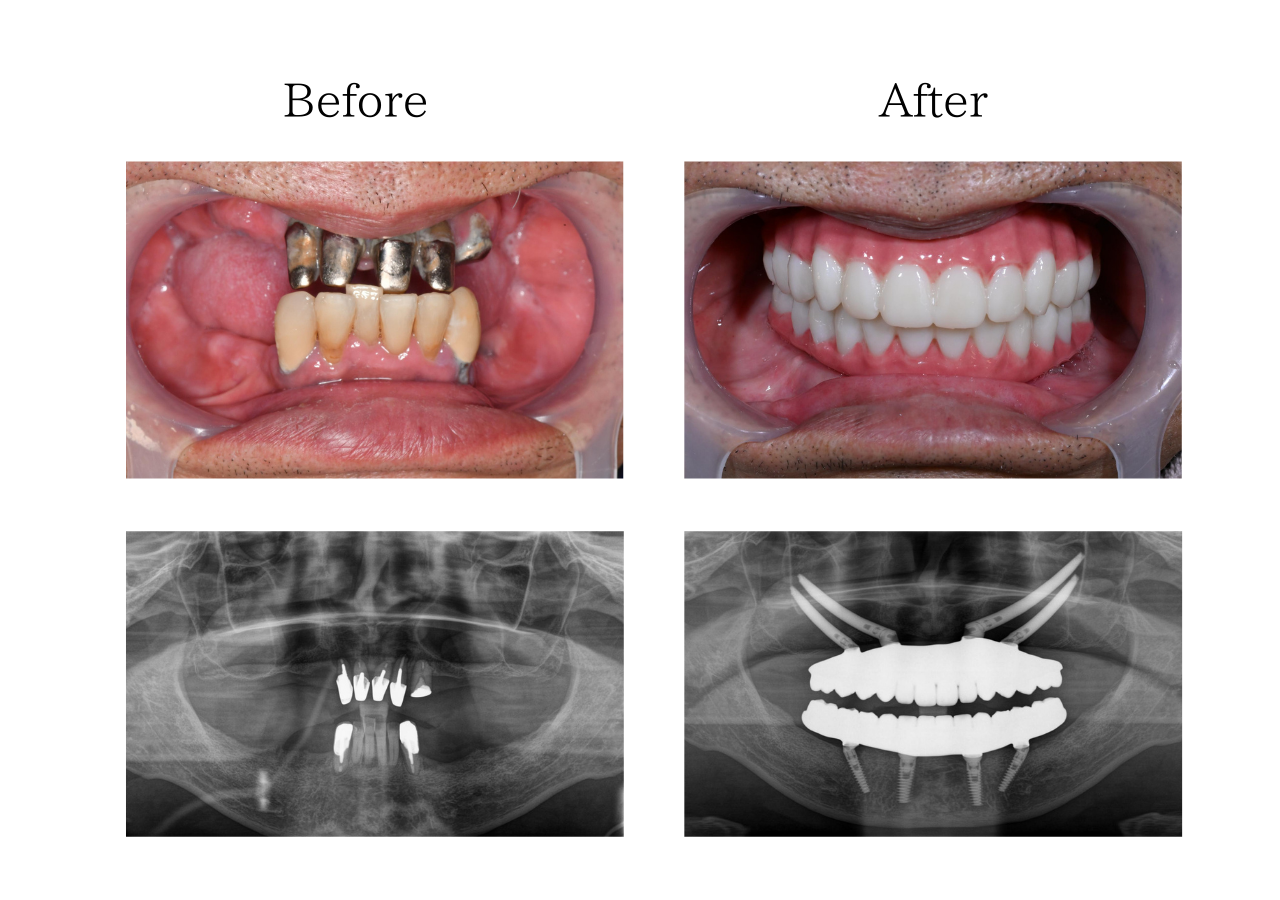

オールオン4 体験談

※治療内容:上下顎オールオン4ザイゴマ4本

※費用:4,795,000円*モニター価格

※期間:半年

※リスク:出血、痛み、腫れ、しびれ

「他院のインプラント治療に不信感」

70代 男性 (福岡) の場合

他院で入れたインプラントは一年くらいで悪くなり抜きました。その後他のインプラントも揺れ始め、その歯科医院に不信感を抱くようになり、最善の治療はないかとネットで調べていたところ、おおたわ歯科医院を見つけました。YouTubeやブログを読んでいて、大多和先生になら任せられると思い相談し、オールオン4の手術を決めました。